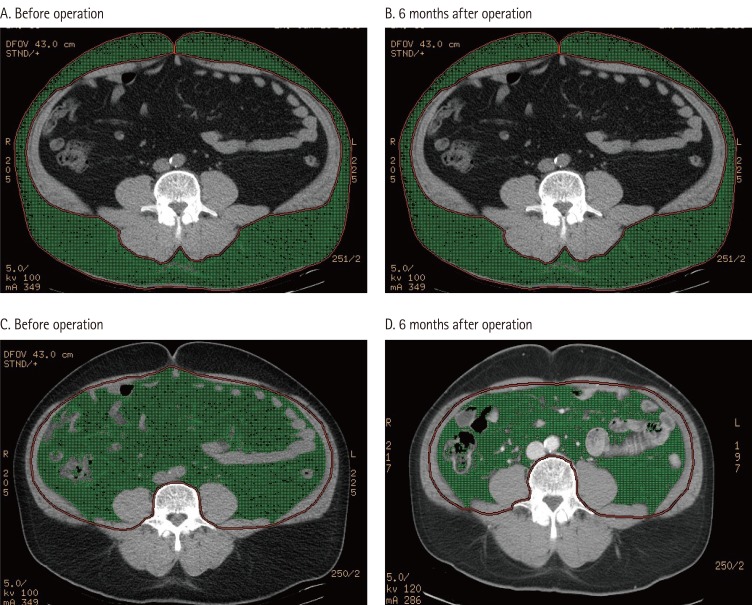

Changes in Fat Intake, Body Fat Composition and Intra-Abdominal Fat after Bariatric Surgery

Bariatric surgery is considered to be the effective treatment alternative conducted over the lifetime for reducing weight in patients with clinically morbid obesity. For many patients, the benefits of weight loss, including decreases in blood glucose, lipids, and blood pressure as well as increase in mobility, will outweigh the risks of surgical complications. But patients undergoing bariatric surgery have the least risk for long-term diet-related complications as reported in several studies. Thus, with an increasing number of severely obese patients undergoing bariatric surgery, the multidisciplinary healthcare system will need to be managed continuously. Many nutrition support specialists will need to become familiar with the metabolic consequences for the frequent monitoring of nutrition status of the patients. South Korea has a very short history with bariatric surgery, and relatively few studies have been conducted on bariatric surgery. Therefore, the

objective

of this report was to compare the nutrient intake, weight loss, body fat composition, and visceral fat before and after the bariatric surgery.